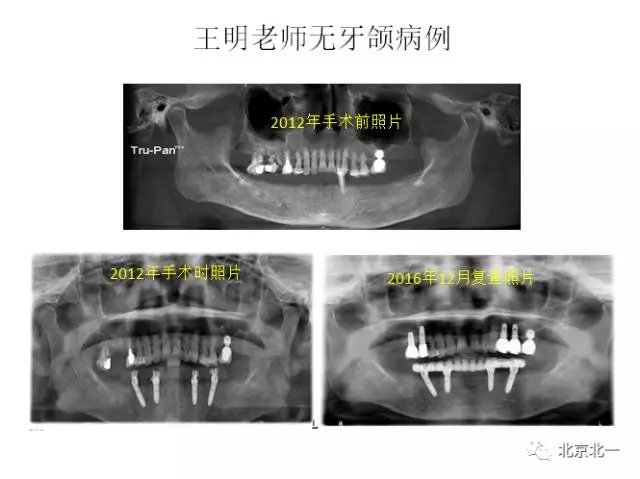

王明

北一種植聯(lián)盟首席專家;

擅長:種植外科,尤其專長復雜牙種植,自體骨移植同期種植,上頜竇底內(nèi)外提升同期種植技術,美學區(qū)種植技術,即刻種植外科與即刻負重技術,軟組織成形外科種植技術及全口無牙頜ALL-ON-FOUR技術,種植并發(fā)癥和種植急癥處置等手術治療,從事口腔頜面外科,正頜外科、頜面部整形、微創(chuàng)拔牙,笑氣無痛舒適種植十余年。

畢業(yè)于中山大學光華口腔醫(yī)學院,擅長各型牙列缺損缺失的種植義齒修復。

2014年榮獲全國第三屆BITC 口腔種植病例大獎賽優(yōu)秀獎。